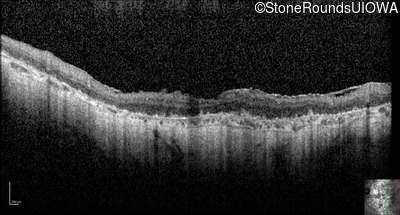

Optical Coherence Tomography - Right - Hand Motion

Exemplar / OCT Stack